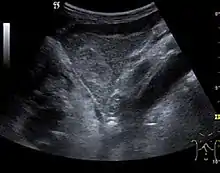

The ultrasound appearance is a well defined lesion, with very thin, almost unapparent walls, without circulatory signal at Doppler or CEUS investigation. The content is transonic suggesting fluid composition. The presence of membranes, abundant sediment or cysts inside is suggestive for parasitic, hydatid nature. Posterior from the lesion the acoustic enhancement phenomenon is seen, which strengthens the suspicion of fluid mass. They typically displace normal liver vessels but no vascular or biliary invasion occurs.

Liver cyst